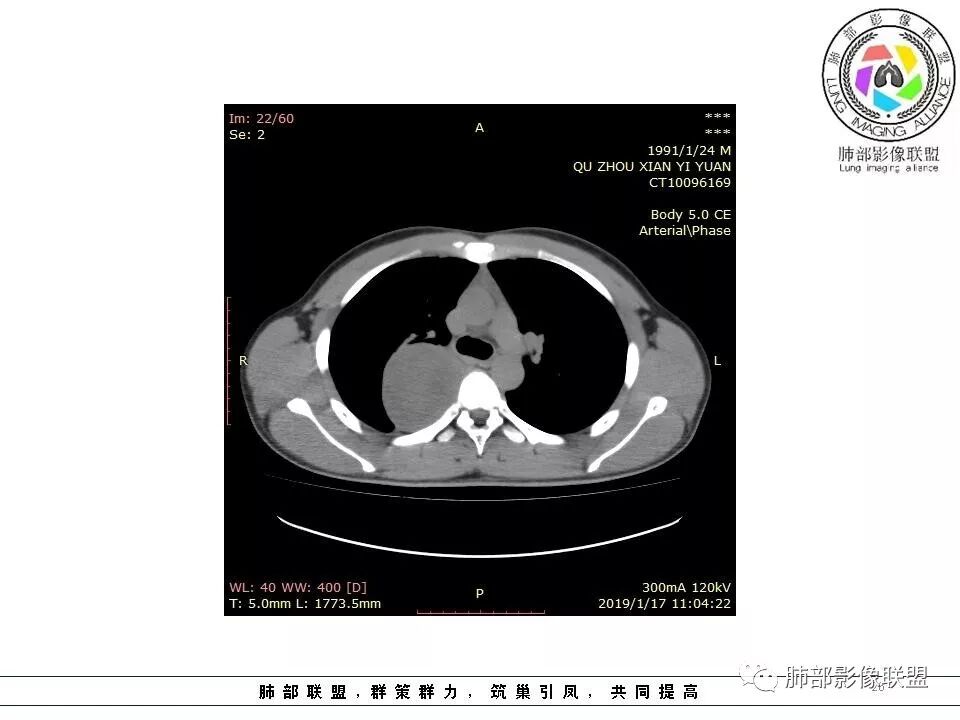

青年男性,间断胸痛;右侧脊柱旁可见一类圆形软组织密度影,密度欠均匀,增强扫描呈轻中度持续强化,邻近肺组织及肺动脉推移,可见肋间动脉供血,部分胸膜下脂肪可见,部分层面似见与右侧椎间孔相连。考虑后纵隔神经源性肿瘤。

后纵隔脊柱旁占位性病变,有胸膜尾征,胸膜下脂肪可见,蛇纹征,明显强化。考虑孤立性纤维瘤。

病灶定位脏层胸膜,肺组织受挤压,有胸膜尾征,动脉期可见血管支配,考虑肺动脉供血,静脉期,强化增强明显,符合快进慢出特点,病灶内可见低密度区,考虑胸膜孤立纤维瘤。

右侧后纵隔脊柱旁占位,边缘光滑清晰,内侧肺组织受压,外侧可见胸膜尾征,增强持续强化,并可见蛇纹血管征。考虑SFT

青年男性,右侧脊柱旁软组织肿块,边缘膨隆,密度不均,临近肺组织受压、胸膜增厚,增强后动脉期呈不均匀强化,并可见肋间动脉供血,延迟期强化较均匀,定位肺外,首先考虑SFT,神经源性肿瘤待排

青年男性,右侧后纵膈肿块,有胸膜尾征,支气管被推压,定位肺外,脏胸膜?血供来自肺动脉及肋间动脉,增强后有强化,蛇纹征,考虑SFT,鉴别鞘瘤

右侧后纵膈肿块,有胸膜尾征,周围肺组织及支气管被推压,定位肺外,脏层胸膜来源,血供来自肺动脉或者支气管动脉,增强后持续渐进强化,蛇纹征,考虑SFT,鉴别鞘瘤。

青年男性,右后上纵隔脊柱旁沟可见团状软组织影,边界清,密度尚均匀,推挤邻近肺组织,胸膜可见掀起,有肺动脉供血,增强轻度蛇皮样强化,纵隔淋巴结未见肿大,邻近骨质未见破坏,胸膜下脂肪间隙消失,考虑SFT孤立性纤维瘤可能性大,鉴别神经鞘瘤,节细胞瘤,建议活检。

青年男性,胸痛,右上纵膈脊柱旁肿块,形态光整规则,支气管被推移,临近的胸膜明显增厚,有胸膜掀起,增强后密度不均匀,可见蛇形血管征,血供似乎有两根血管供血,考虑SFT

青年男性,瘤肺边界锐利,气管向前推移,定位肺外,局部胸膜增厚,后方见少量积液,提示脏层胸膜来源,增强持续渐渐进性强化,内见蛇纹血管,考虑sft

右侧脊柱旁肿块,边界清晰,密度尚均匀,宽基底,后方见胸腔积液,定位于肺外。增强后不均匀强化,考虑sft。鉴别神经源性肿瘤。

边缘光滑,宽基底与胸壁相连,跨叶裂,叶裂稍前推,血管、支气管前移。

外上侧少量胸水

肋间动脉供血,强化尚均匀,逐步强化

1.右上胸内脊柱旁类圆形肿块,质地似乎比较坚实,密度稍显不均,但未显示明确的坏死。

2.肋间动脉病供血也提示肿块来自后纵隔?